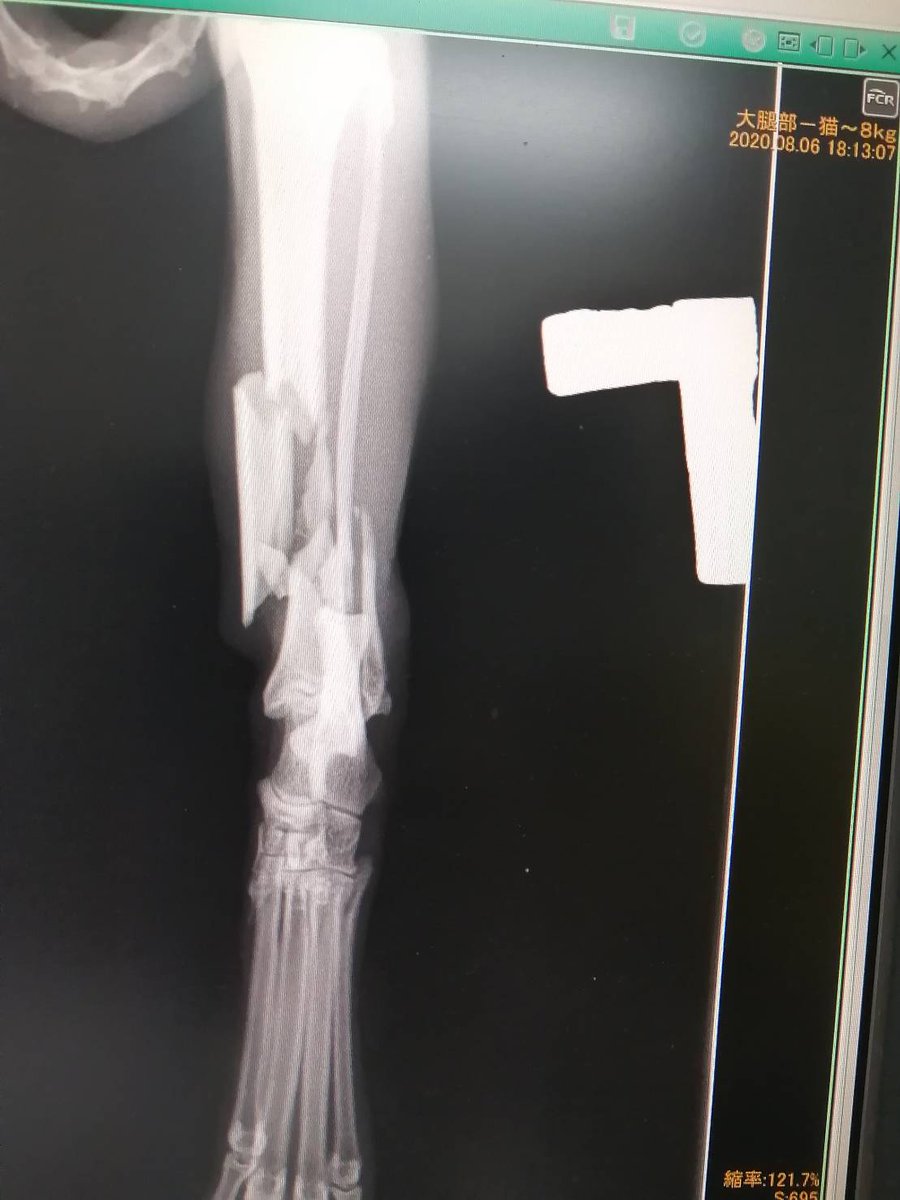

久留米で複雑骨折の子が保護されています。 とてもきれいな子 この子をごぞんじの方いらっしゃいませんか